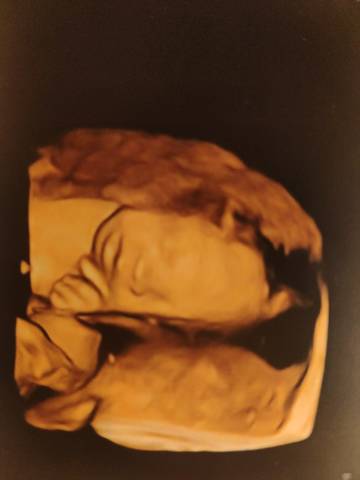

宝宝能看出来面相吗?真的很好奇

journal_insert_pic_1719368539

亲爱的,通过这些判断不出来的哈,反正宝宝发育好就是最好的哈,祝你心想事成。加油

你好。根据数据图片看不出来的。是不科学依据的,孕期定期检查,只要宝宝健康就好。祝心想事成。